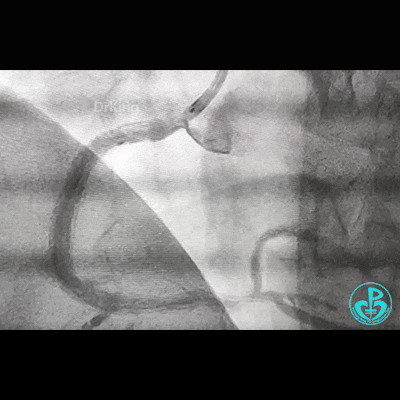

开始后扩,3.5×15mm后扩球囊不能进入近端支架口,GC系统飞出!故事开始。

重进导丝,比较顺利!3.5×15mm球囊仍不能通过支架近段!再进一根导丝,还不行!

考虑导丝可能从支架钢梁外进入,故调整GC,把两根导丝均Knuckle进入,再进球囊!不行!

因右锁骨下动脉迂曲打弯,GC张力过高,尝试GC深插,有阻力,不敢粗暴,稍微提出到开口,则立即飞出!